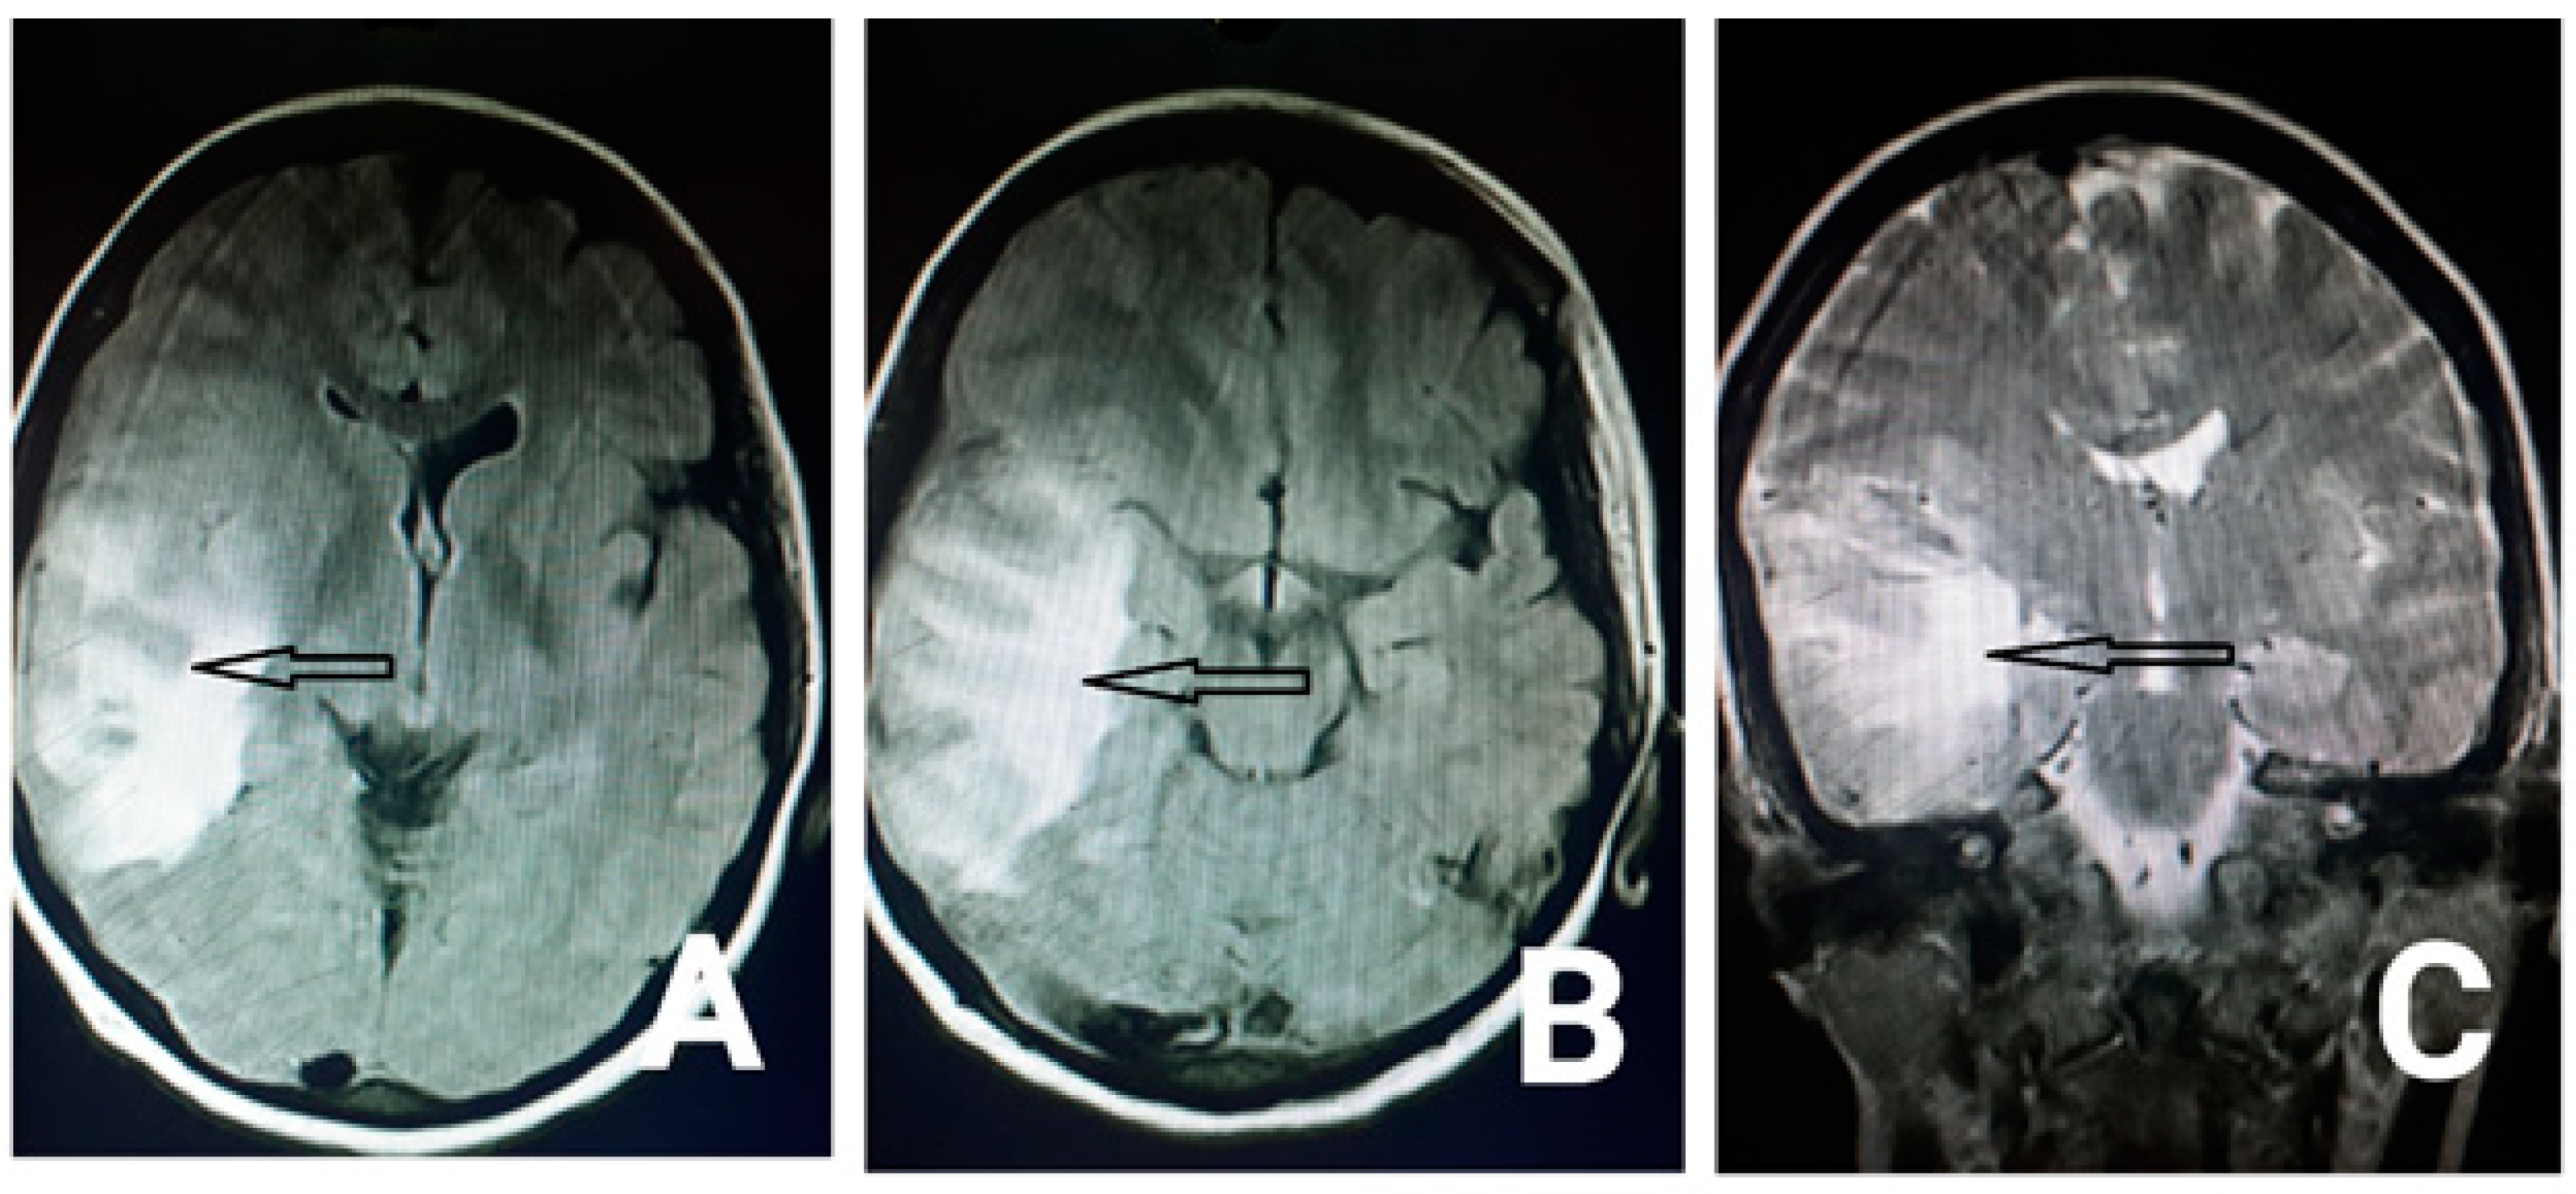

2. Case Presentation